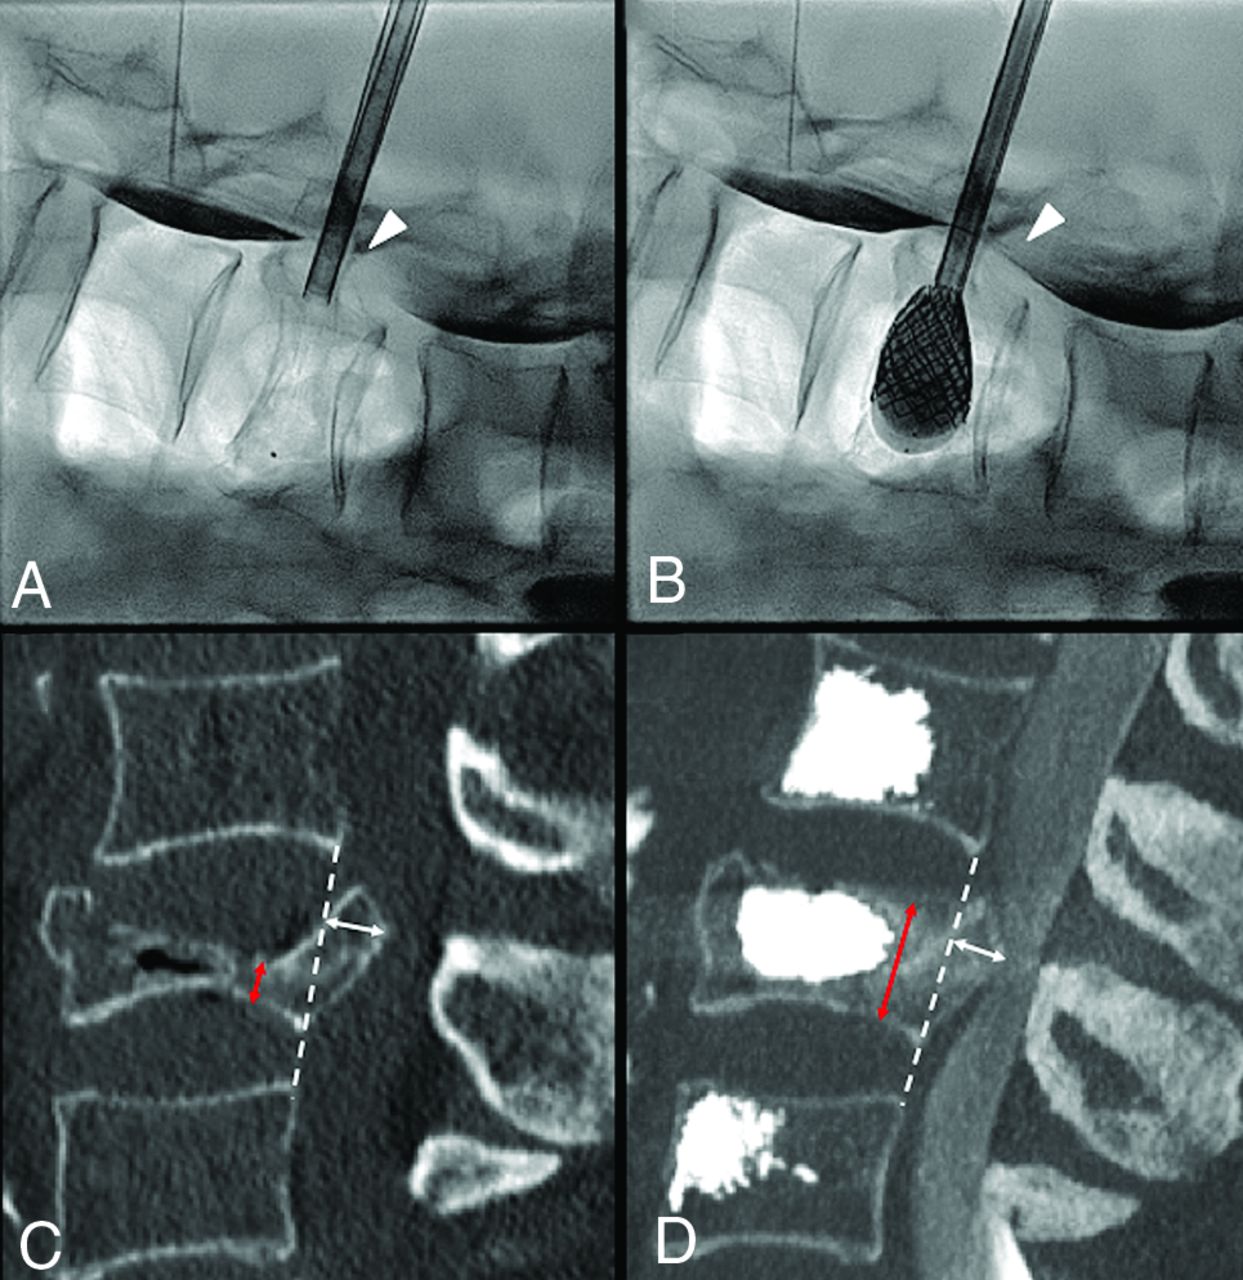

Severe L3 vertebral body collapse (A) in a 74-year-old woman with osteopenia following minor trauma. Intraoperative myelogram through intradural injection of contrast agent at L1–L2 (arrow, A) shows an opacification defect of the dural sac dorsal to the retropusled fragment at L3 (arrowhead, A). On fracture reduction through balloon-expanded vertebral body stents (B), the myelogram shows greater opacification of the dural sac at L3 (arrowhead, B), a real-time indirect sign of ligamentotaxis and partial central canal clearance. C and D, Preoperative and postoperative midsagittal CT images used for measurement of vertebral body height at the maximum point of collapse (red arrows) and of posterior wall retropulsion (white arrows) perpendicular to the dashed white line connecting the postero-inferior corner of the cranial vertebral body and the postero-superior corner of the caudal one, representing the expected original posterior wall, now intersecting the PWR.

Lung cancer metastatic T4 fracture in a 67-year-old man, with disabling back pain. MR imaging (A) and CT (B) show a lytic lesion, with vertebral body collapse and retropulsion of an osseous fragment (arrowhead, B), causing spinal cord compression, but the patient was neurologically intact. The patient underwent armed kyphoplasty with the SAIF technique (C–E) with bilateral stent and screw implant, with a decompressive surgery backup plan on standby. The procedure was uneventful, and the patient showed no neurologic worsening. Postoperative CT (F–H) shows a 3D view of the stent-screw-cement complex (F) and, most notably, the vertebral body height restoration and correction of posterior wall retropulsion (arrow, H) through ligamentotaxis. The patient was ambulating the same day and could undergo radiation treatment during the following days.